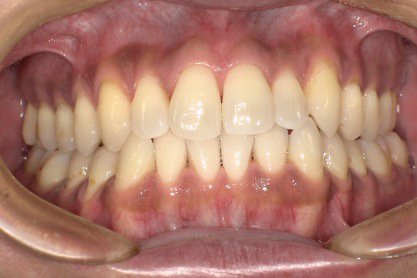

■症例3

Before

After